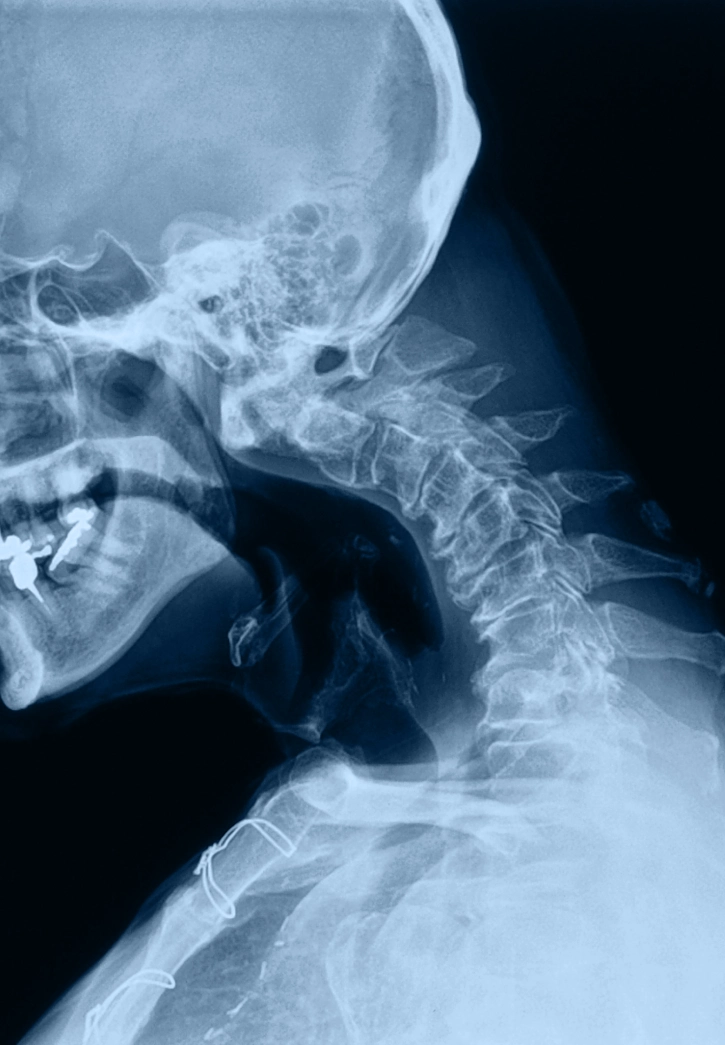

Radiculopathy

What is it?

Radiculopathy occurs when a spinal nerve root is compressed or inflamed, causing radiating pain, numbness, tingling, or weakness.

How it Happens?

Herniated discs, bone spurs, stenosis, or degenerative changes that narrow nerve exit pathways.

Symptoms

Cervical radiculopathy: neck pain into shoulder/arm/hand

Lumbar radiculopathy: low back pain into buttock/thigh/leg/foot